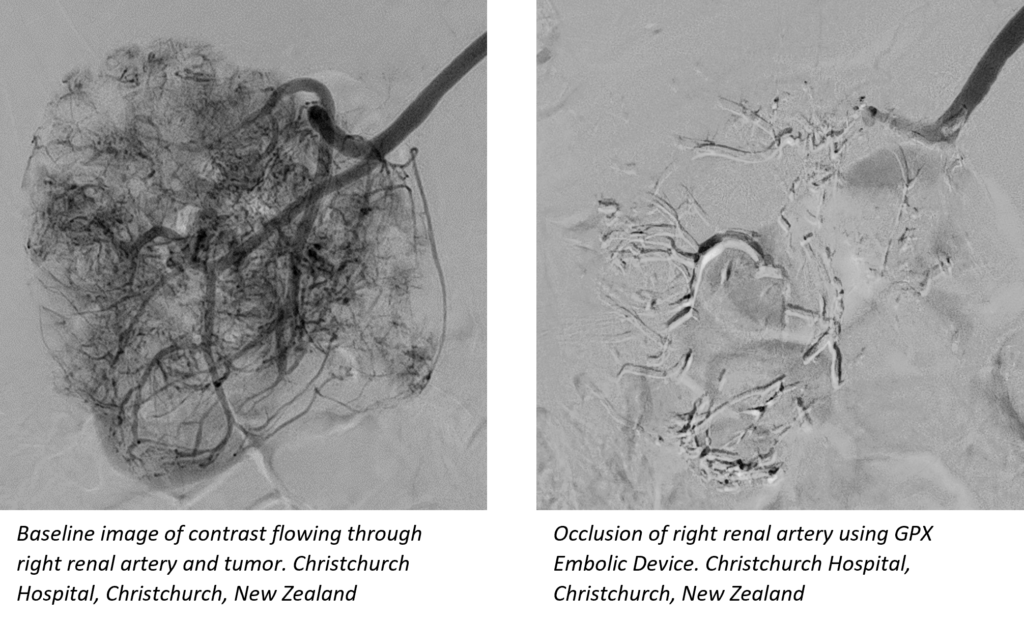

Salt Lake City (UT) – Fluidx Medical announces the completion of a multi-center clinical trial examining the broad application of their new liquid embolic agent, GPX®. Embolization is a procedure in which arterial or venous blood supply is intentionally blocked.

“In the study, GPX was successfully used to treat a range of hypervascular tumors as well as other arterial and venous applications”, stated Martin Krauss, M.D., Head of Interventional Radiology at Christchurch Hospital. “The embolic flowed nicely, providing excellent control and beautiful filling of distal branches.”

A common concern with liquid embolics is that the delivery microcatheter tip may become entrapped in solidifying embolic following deployment. But the unique GPX material does not entrap existing delivery microcatheters, and no entrapment was observed during the study. Because clinicians weren’t concerned with GPX-caused microcatheter entrapment, they were able to take their time during material delivery to ensure complete occlusion of the targeted region.

GPX technology is a low viscosity, aqueous-based solution that solidifies into a durable embolus upon delivery without polymerization or dimethyl-sulfoxide (DMSO) precipitation.* The platform is expected to bring simple preparation and controllable material delivery to several embolic applications. The device is packaged in a ready-to-use syringe, can be prepped tableside by the clinician in about 30 seconds, and may be delivered through standard microcatheters (no complex mixing systems or special delivery catheters are necessary).